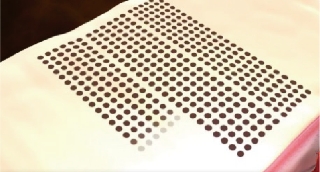

Thermal stimulation of entire vaginal wall layer

Immediately after treatment, shrinkage of the vaginal skin fibers occurs. In addition, collagen growth is promoted and the vaginal wall becomes resilient and thick. Changed Vaginal structure after treatments makes its whole conditions better.

Effect of Laser Treatment Collagen Stimulation

- Vaginal Remodeling

- Vaginal Dryness

- Sexual Dissatisfaction

- Pelvic Organ Prolapse

- Urinary Incontinence

Fractional Handpiece

Before the treatment Loosen vagina inner wall